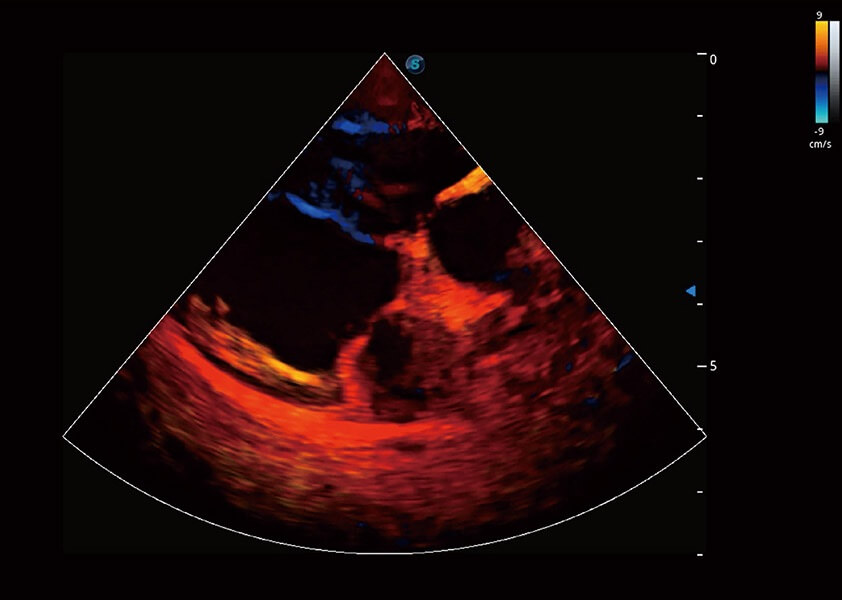

ProPet 60 作为一款高端台式动物超声设备,为动物医生的日常诊断提供了一系列贴合动物临床需求、解决临床实际问题的高级成像功能。凭借全系列高清探头,满足医生对腹部、心脏、生殖、浅表、肌骨等成像的所有需求,切实帮助您提升检查效率,提高诊断信心。

动物是人类最亲密的朋友和最值得信赖的伙伴。环球UG官网也一直致力于探索动物专用的超声影像解决方案。 全新推出的ProPet系列,是环球UG官网在动物超声影像智能化、专业化、精准化的一次跨越式革新。动物不能用言语来表述自己的不适,通过超声影像,ProPet系列搭建了动物医生与不同物种沟通的“桥梁”,为动物医生注入了“治愈之力”。